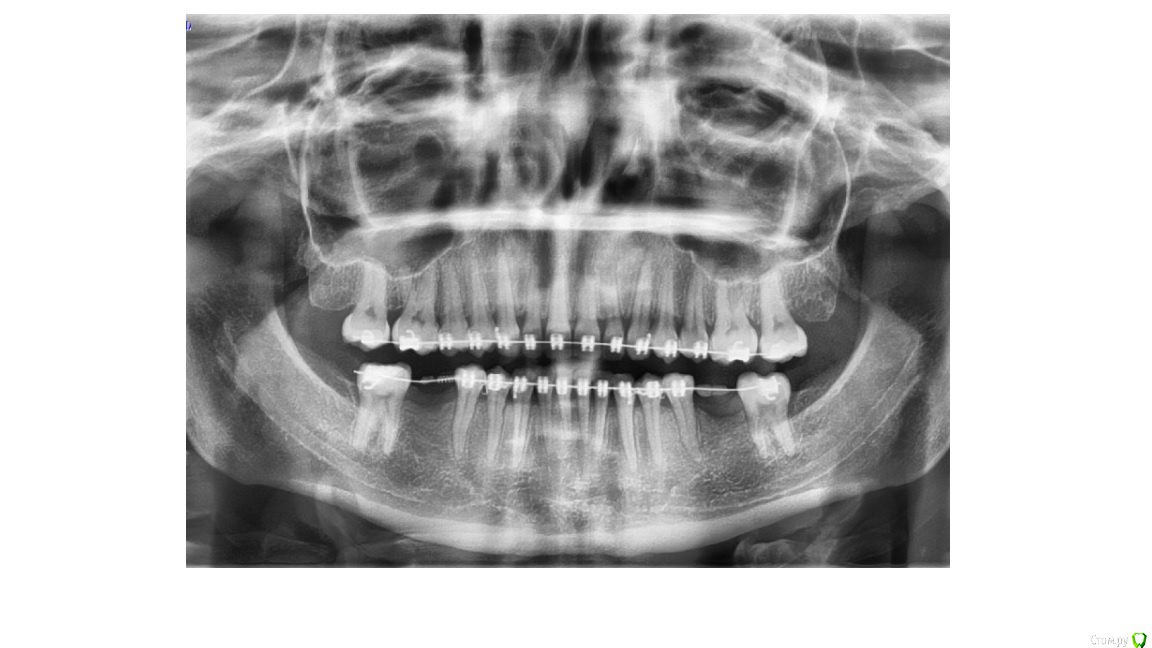

my_evid Опубликовано 15 ноября, 2019 Поделиться Опубликовано 15 ноября, 2019 Здравствуйте! Прошу высказать свое профессиональное мнение на мою ситуацию. Заканчиваю ортодонтическое лечение, 15 лет отсутствуют 46 и 36, мне сообщили о необходимости установки имплантов для дальнейшего сохранения результата. В итоге у трех хирургов разное мнение на этот счет: 1. необходима костная пластика по бокам и под имплантатом (с установкой костного блока) (вроде)2. костная пластика необходима по бокам3. костная пластика не нужна. Как мне объяснил врач, придерживающийся третьего варианта, костная пластика необходима в моем случае для того чтобы коронка была одинакового размера с остальными зубами, это важно только для эстетики, на жевательную способность это не влияет, а так, есть возможность имплантат вогнать глубже и обойтись без этой операции.Врач, придерживающийся второго варианта, сказал что тоже сделаем глубже имплантат, коронки будут отличаться по высоте, но пластика нужна по бокам, как я поняла, непосредственно для его установки.Так как это дополнительные средства и дополнительное вмешательство, не знаю как поступить. Сделала скрин КТ, надеюсь что-то будет ясно. Ссылка на комментарий